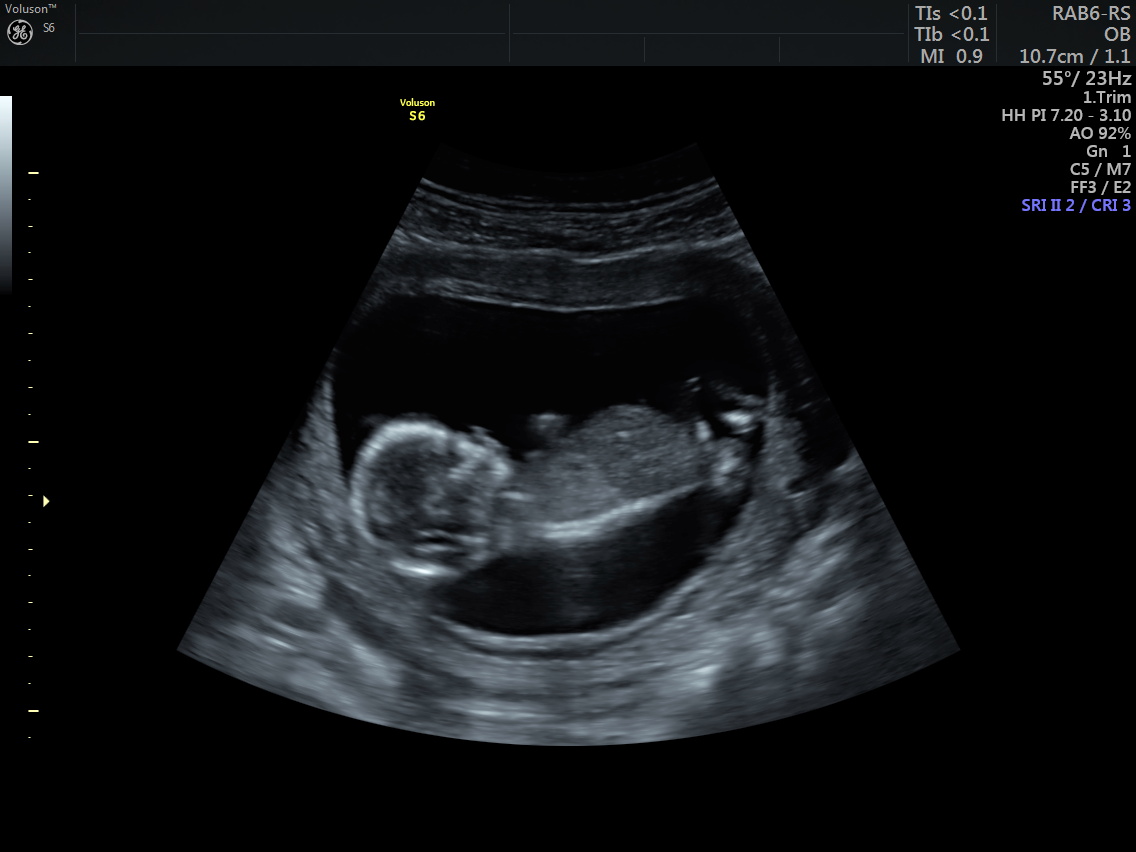

Merhaba, bizim cinsiyet hala kesinleşmedi 🙂 ben biraz nubu araştırdım. Ve size ilk gönderdiğim resimde nub kısmının dik olduğunu gördüm. Ama aynı anda verilen diğer görüntü aşağıda fakat burda da nubu paralel gözüküyor. Kafam karıştı açıkcası. Hangisi sizce?

Ekli dosyalar

• IMG-20210215-WA0022.jpg

IMG-20210215-WA0022.jpg

139,6 KB · Görüntüleme: 432

Emin olmamakla birlikte kız gibi görünüyor canım umarım sağlıklı kucağına alırsın sonucu kesin öğrendiğinde de yazarsan sevinirim :hamis: :d040: